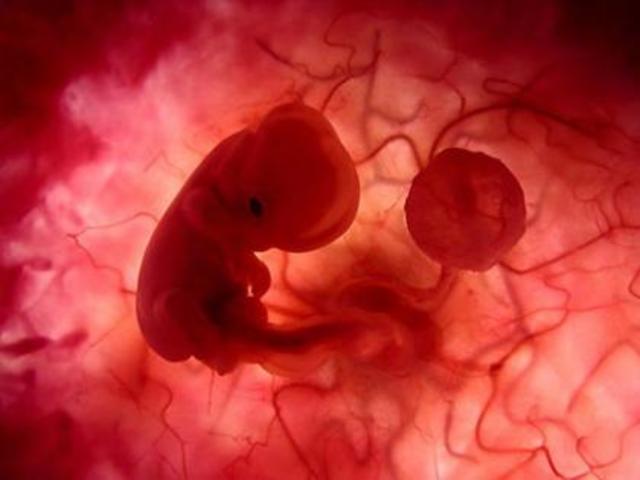

• semana 3, 4 y 5 de embarazo

semana 3, 4 y 5 de embarazo

En la semana tres se empieza a formar el sistema nerviso el embrión está formado por 3 capas célulares, la capa superior el ectodermo, donde se desarrolla el cerebro y varias regiones del sistema nervioso central, así como la epidermis las glándulas de la piel, uñas y el pelo. La capa media el mesodermo de donde cxrece el corazón, el sistema circulatorio, los huesos, los músculos, los riñones y los órganos de reproducción y por último la tercera capa mas interna , el endodermo, que es un tubo.

• semana 8 y 9 de embarazo

semana 8 y 9 de embarazo

Hacia el final de la semana 8 el cuerpo estará formado, así como tosoa sus órganos y terminará el periodo embrionario. Dejará de ser un embrión para convertirse en feto en la semana 9 crecen los dedos de las manos y de los pies. La cabeza es desproporcionalmente grande y construye la mitad del embrión. La región del cuerpo se ha formado. T5iene un cuerpo muy flexible ya no tiene huesos.